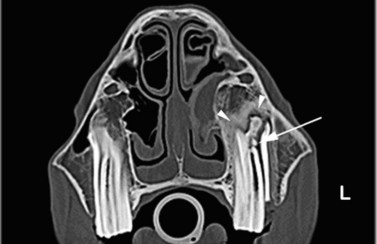

image image image

Fig. 13.43 Radiograph (A) and CT images (B and C) of a compound odontoma in a 2-year-old TB colt.